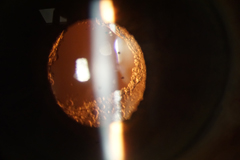

![]() 白內障 |

![]() 術後第一日 |